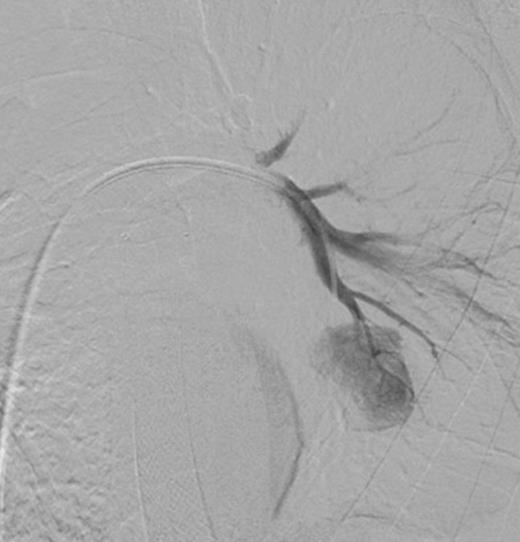

Left pulmonary artery digital subtraction angiography image demonstrating filling of left lower lobe aneurysm (arrow)

Two weeks later he re-presented with fever and shortness of breath. CT-thorax demonstrated a left lower lobe cavity containing a 14mm segmental PAA. Contrast-swallow confirmed oesophageal perforation at the site of the oesophageal stricture in continuity with this cavity. This was drained percutaneously under radiological guidance and a partially-covered MicroTech® stent was inserted to control the oesophageal leak. Culture of the abscess cavity pus grew Candida albicans which was treated with appropriate antimicrobials. The pulmonary cavity reduced in size on serial CTs and he was discharged home.

Three days later he presented with significant haemoptysis. A CT pulmonary angiogram (CTPA) demonstrated an increase in size of the PAA from 14mm to 28mm (Figure 1) diameter. A radiology opinion was sought and the patient transferred to the angio-suite for intervention.